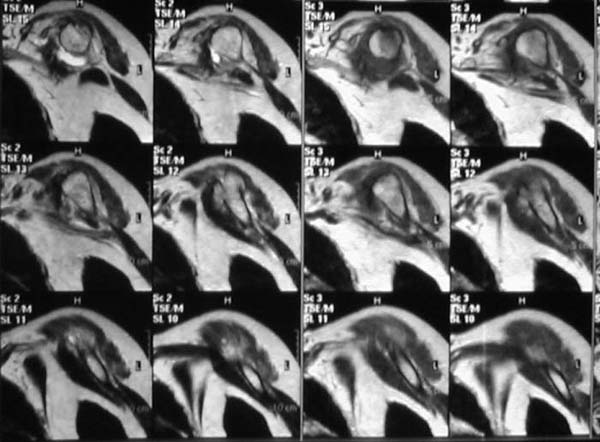

Уважаемые коллеги!Женщина, 60 лет. 3 недели назад упала с упором на отведенную левую руку. Почувствовала боль в левом плечевом суставе. За помощью не обращалась. 2 недели "мази и припарки". Затем - рентгенограмма (r1 и r2), жалобы на боли,ограничение движений...

Активное отведение 80 гр., при пальпации - головка плечевой кости безболезненно вправляется и тут же самостоятельно вывихивается. Наложена косыночная иммобилизация, рентгенография (r3) и МРТ.В нашем диагностическом центре МРТ исследование плечевого сустава выполнено впервые, опыта у нас маловато :(.Вопросы: уточнение диагноза? какие исследования провести? тактика лечения?

Из того, что видно на недостаточно качественно отсканированных МРТ - нижний подвывих плеча и синовиит. Непонятный очаг по заднему контуру головки плеча (то ли артефакт, то ли косой срез, проходящий между головкой и большим бугорком). Сухожилия вращательной манжетки выглядят целыми. Неправильная форма нижней части labrum glenoidale - разрыв ?

И еще одно пожелание - МРТ костно-суставной системы ОБЯЗАТЕЛЬНО нужно проводить с использованием сканов с подавлением сигнала от жировой ткани (SPIR - на Филипсах, у Вас, как я вижу - Филипс; FATSAT - на других томографах, либо STIR - есть на любых аппаратах). Только так можно увидеть отек мягких тканей и костного мозга на фоне жировой ткани.

Плоскости при сканировании плеча обязательно должно быть 3

1. Ортогональная поперечная (аксиальная)

2. Косая корональная (параллельно длинной оси диафиза)

2. Косая сагиттальная (так же параллельно диафизу плеча)

МРТ должен показать разрыв манжетки, но признаться я не большой эксперт по чтению МРТ сканов, хотя затемнение, отек мягких тканей по задней поверхности плеча видны Обычные рентгенограммы демонстрируют остеолизис в области большого бугорка.

1. На рентгене - нижний подвывих плеча и очаг остеолиза суставного бугорка с четкими контурами (вдавленный перелом на фоне остеопороза ? доброкачественная опухоль? аваскулярный некроз ? (хотя ни разу не слышал об аваскулярном некрозе плеча..)

2.выраженный выпот в полости сустава

3. Сказать о связках и сухожилиях что-то при снимках в таком режиме не берусь.

Судя по снимкам, речь идTт о типичном случае Hill-Sachs Lesion. По этому поводу я позволю себе некоторый экскурс:

97 % всех вывихов плеча происходит по механизму комбинации отведения, разгибания и наружной ротации (А. Гринспан). В момент вывиха головка плеча ударяет о нижний край гленоида, что ведет к вдавленному или компрессионному перелому одной или обеих структур. Чаще всего, однако, повреждение возникает в задней латеральной области головки плечевой кости на переходе от головки к шейке. Этот диагноз можно выставить на основании рентгеновского снимка в переднезадней проекции с внутренней ротацией плеча. Несколько реже видно повреждение гленоида о передненижний перелом края. То, что мы называем Bankart Lesion. Это повреждение видно на ре. снимке в п.з. проекции при нейтральной позиции плеча. Разумеется хрящевые и мягкотканные повреждения (в смысле Банкарт) мы увидим лучше всего на ЯМР.

Учитывая описанную клинику, речь идTт о комбинации патологии. К сожалению, учитывая качество снимков NMR, я не могу провести достаточно точную верификацию состояния нижнего края гленоида, что впрочем, не меняет рекомендации. Для определения состояния РМ и дополнить исследование УЗИ мягких тканей плеча. В опытных руках достаточно информативное и дешевое исследование.